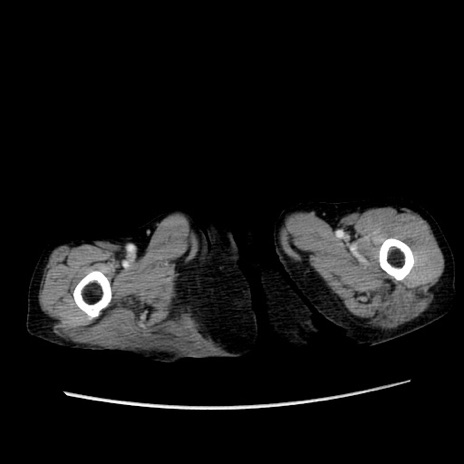

冠状断像

【症例】80歳代女性

【主訴】胸のつかえ感

【現病歴】約9時間前に食後から胸のつかえた感じあり、嘔吐あり、来院。

【既往歴】胃癌(全摘)、胆摘、虫垂炎

【身体所見】心窩部に圧痛あり、反跳痛なし。

【データ】WBC 5700、CRP 0.05